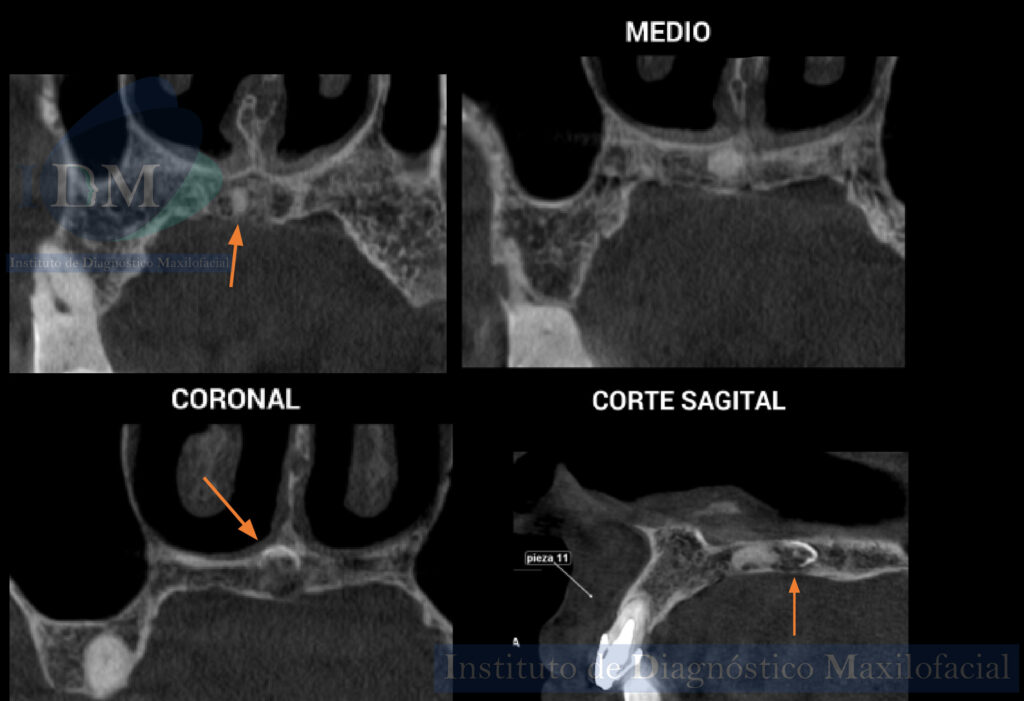

A la evaluación de la tomografía computarizada de haz cónico de campo mediano (10 x 10) se aprecia un hallazgo imagenológico no observado en la radiografía panorámica.

En cortes axiales se puede observar la presencia de una pieza supernumeraria rudimentaria localizada a nivel del tercio medio del paladar duro del lado derecho adyacente a la sutura intermaxilar. La porción coronaria se orienta hacia la espina nasal posterior y el tercio apical hacia anterior con ensanchamiento de espacio para el ligamento periodontal apical. Asimismo, en los cortes axiales, coronales y sagital se evidencia la pérdida de continuidad de la superficie coronaria y la alteración en su morfología caracterizada por la presencia de imágenes hipondesas, signos imagenológicos compatibles con ameloclasia.

CORTES AXIALES

CORTES CORONALES